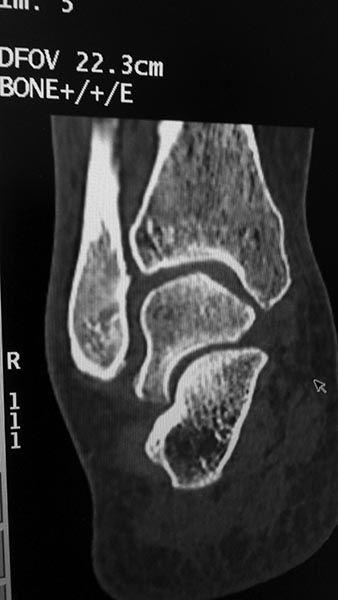

Добрый день!Обратилась женщина 1975 г.р. Жалобы на боль в голеностопном суставе при нагрузке (после ходьбы на расстояние 200 метров).

Травма три года назад. Упала с высоты своего роста, подвернула ногу, лечилась амбулаторно с Ds : растяжение связок голеностопного сустава. Rg не делали. После травмы боль осталась, в динамике интенсивность боли прогрессировала. Ухудшение в течении последних 6 мес. Местно : движения в голеностопном суставе в полном обьеме, отек незначительный. Пальпация безболезненна.Rg, Кт прилагается.Какова на ваш взгляд тактика лечения в данном случае?

Я бы еще повниматьнее к таранной кости присмотрелся. Не было ли перелома ее шейки? На КТ срез подозрительный, но только один.

Я тоже согласен, на одном из КТ-снимков, подозрение на перелом шейки таранной кости.

Также есть подозрение на перелом таранной кости по КТ.